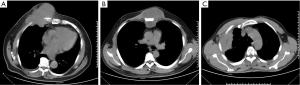

Titanium mesh was used when the defect in the chest wall was larger than 6 cm or ≥3 ribs. Before surgery, emission computed tomography (ECT), chest computed tomography (CT) scan (Figure 1) and pulmonary function tests were routinely used in all patients. The metastatic work-up was undertaken to eliminate an extrathoracic metastatic lesion. A total of 27 patients were identified, forming the basis of this review. Patients’ and tumors’ records were collected.

Double-lumen endobronchial tube was inserted following general anesthesia. The chest wall tumors and involved chest wall (including ribs and adjacent soft tissue) with at least 4 cm margin were totally removed (Figure 2). Subcutaneous tissue and skin were not removed. For relatively small resections, direct closure is performed, given that skin and subcutaneous tissue can be preserved with a good blood flow so that a titanium mesh can be safely covered. For lager defections, regional pedicled muscular or musculocutaneous flaps were used as choice for soft tissue coverage of the titanium meshes. Microscopic evaluation of the margins by frozen section was not routinely made due to wide resection. Titanium mesh prosthesis [Timesh (Flexmesh), Medtronic neurologic technologies] with tailored size was placed in the defect. Each side of the prosthesis overlapped the edge of the defect by 1-2 cm and was fixed with steel wires around the end of the resected ribs and/or sternum, as shown in Figure 1. The chest cavity was drained with a 28F chest tube. Subcutaneous drainage was not used in the mesh site. Pressure dressing was routinely used while not respiratory support postoperatively.

Table 4 summarized the postoperative follow-up course of all patients. The mean follow-up was 30.7 months (median 30.0 months, range, 4-62 months). All patients were seen every 3 months in the first year and then every 6 months, showing satisfactory cosmetic and functional outcomes (Figure 3A). During the course, none of the patients had experienced paradoxical respiratory motion or wound infection or skin necrosis. Furthermore, there was no mesh dislocation (Figure 3B-D). All patients performed VAS for pain measurement showed ‘excellent’ or ‘good’ outcomes points (median 3, average, 2.7). At the last follow-up, 23 patients were alive (19 with initially primary lesions and 4 with initially secondary lesions). Of those, two cases with local recurrence (one with fibrosarcoma and one with desmoid tumor) were observed at 52 and 27 months, respectively. Four died (two with initially primary disease including one with osteosarcoma, and one with sternal plasma cell tumors; two with secondary disease including one with Hodgkin lymphoma and one with squamous cell lung carcinoma). One died of both local recurrence and distant metastasis. Three cases of death were unknown. The 5-year DFS and OS of primary chest tumors was 72.1% and 80.8%, respectively (Figure 4).